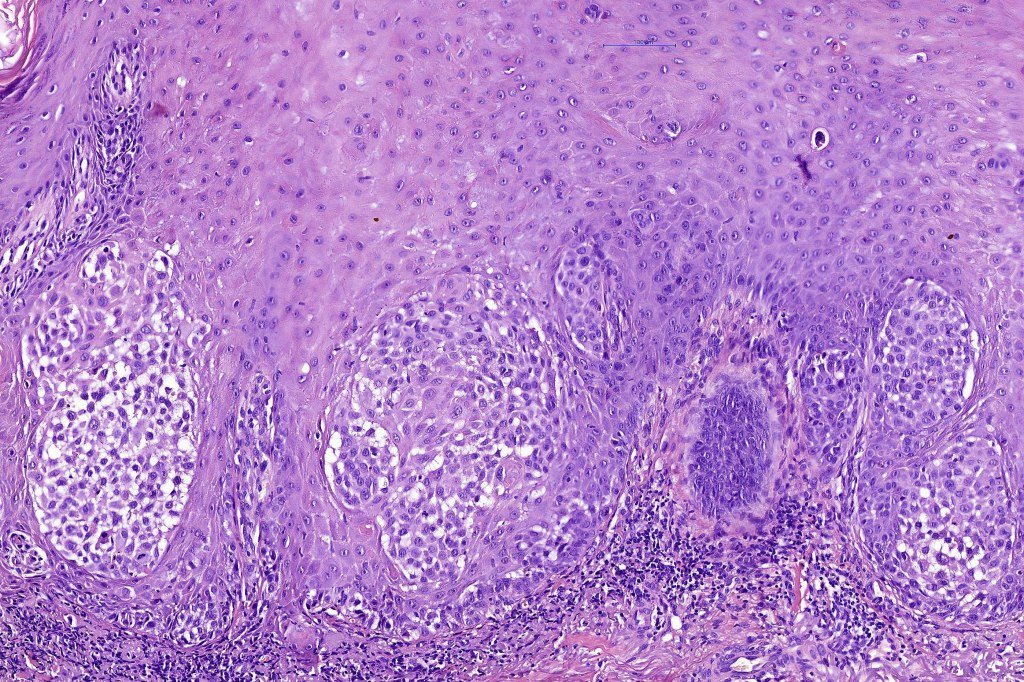

Histological features

•Hyperkeratosis, parakeratosis & acanthosis

•Full thickness dysplasia (carcinoma in situ) involving the epidermis and intraepidermal adnexal elements

•Loss of maturation, nuclear pleomorphism, marked mitotic activity +/- abnormal forms

•Dyskeratosis & apoptosis

•Nested (clonal, Borst-Jadassohn) variant